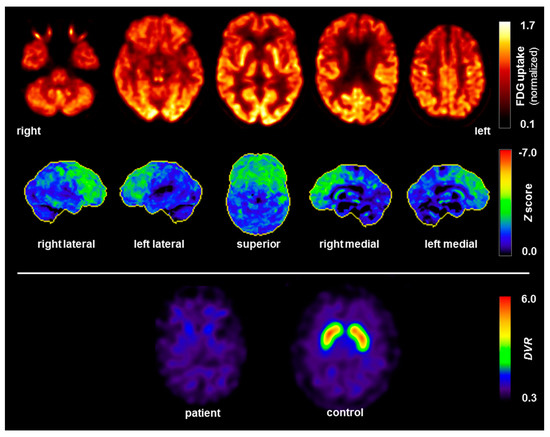

| [123]FPCIT single-photon emission computed tomography (FPCIT SPECT) |

- The anti-GlyR antibodies could have been generated first, thereby triggering a clinical phenotype as a Parkinsonian syndrome with frontal lobe involvement. This is conceivable in principle, but very unlikely in the presented patient; no typical signs of autoimmune anti-GlyR antibody syndrome presently known (e.g., hyperexcitability, anti-GlyR antibodies in CSF, or other inflammatory CSF changes) were detected [17]. Furthermore, the instrument-based diagnostics, using EEG, MRI and FDG PET, as well as the poor response to anti-inflammatory treatment did not support the hypothesis of underlying autoimmune encephalitis.